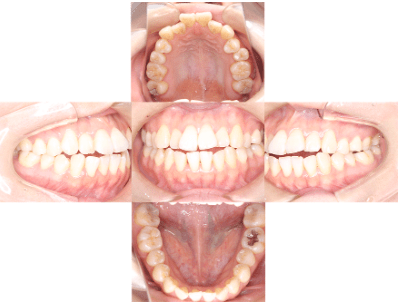

治療後

• 初診時年齢:25歳

• 主訴:開咬

• 診断:舌癖を伴う歯性の開咬、非抜歯

• 治療内容:下で前歯を押してしまい、前歯で咬めない状態でした。マウスピース型カスタムメイド矯正歯科装置(製品名インビザライン 完成物薬機法対象外)で、奥歯を低くしつつ、前歯を伸ばし、前歯で咬めるようになりました。

• 治療期間:2年6ヶ月

• リスク:ブラックトライアングル(歯と歯の間と歯ぐきの間の三角形の隙間)が強くでる場合がある

• 費用:90万円